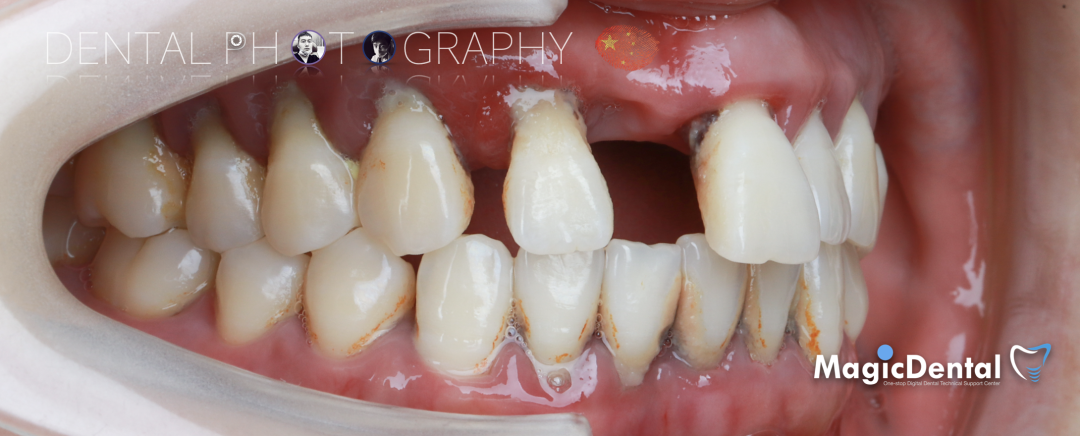

患者术前口内及面相照片

口腔检查:口腔卫生差,全口牙龈红肿,牙颈部大量牙结石附着,伴有不同程度附着丧失,牙周探针深度普遍大于8mm,上颌牙列I~III°松动。

CT显示牙槽骨水平吸收严重,大多数吸收至根尖。

诊断: 全口慢性牙周炎,上颌牙列缺损。

治疗计划:拔除上颌牙列,种植6枚奥齿泰种植体,马龙桥修复。下颌行牙周治疗+纤维带固定。